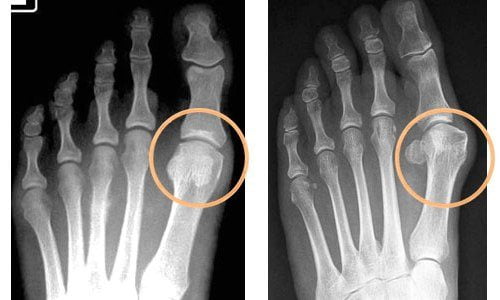

- рентгенография;

Диагноз устанавливается на основании характерных симптомов и данных обследования. Стандартный метод диагностики – рентгенография. При ревматоидном артрите выделяют 4 рентгенологические стадии:

- 1 – определяется отек мягких тканей, признаки остеопороза;

- 2 – появляются единичные костные эрозии (узуры);

- 3 – эрозий становится больше;

- 4 – между суставами образуются анкилозы.

При подагре обнаруживают суставные деформации, солевые отложения в мягких тканях.